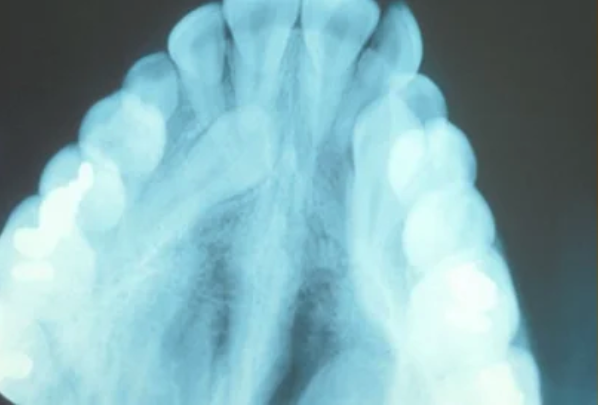

Normally, the maxillary cuspid teeth are the last of the “front” teeth to erupt into place. They usually come into place around age 13 and cause any space left between the upper front teeth to close tighter together. If a cuspid tooth gets impacted, every effort is made to get it to erupt into its proper position. The techniques involved to aid eruption can be applied to any impacted tooth in the upper or lower jaw, but most commonly they are applied to the maxillary cuspid (upper eye) teeth. Sixty percent of these impacted eyeteeth are located on the palatal (roof of the mouth) side of the dental arch. The remaining impacted eye teeth are found in the middle of the supporting bone, but are stuck in an elevated position above the roots of the adjacent teeth, or are out to the facial side of the dental arch.

The older the patient the more likely an impacted eyetooth will not erupt by natural forces alone, even if the space is available for the tooth to fit in the dental arch. A panoramic x-ray, along with a dental examination, will help determine whether all the adult teeth are present or if some adult teeth are missing.

In cases where the eyeteeth will not erupt spontaneously, the orthodontist and oral surgeon will work together to get these teeth to erupt. Each case must be evaluated on an individual basis, but treatment will usually involve a combined effort between the orthodontist and the oral surgeon. The oral surgeon will expose and bracket the impacted eyetooth.